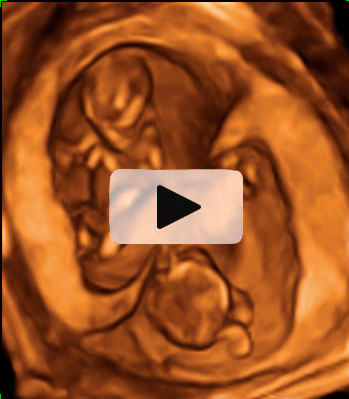

Ecografía Embarazo 4D Semana 12 - ANOMALÍAS CROMOSÓMICAS